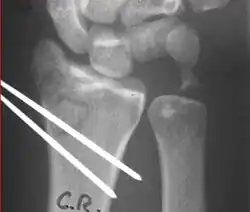

A Colles fracture as seen on X-ray: It is a type of distal radius fracture.

X-rays of pins across a distal radius fracture: Notice the ulnar styloid base fracture, which has not been fixed. This patient has instability of the DRUJ because the TFCC is not in continuity with the ulna.